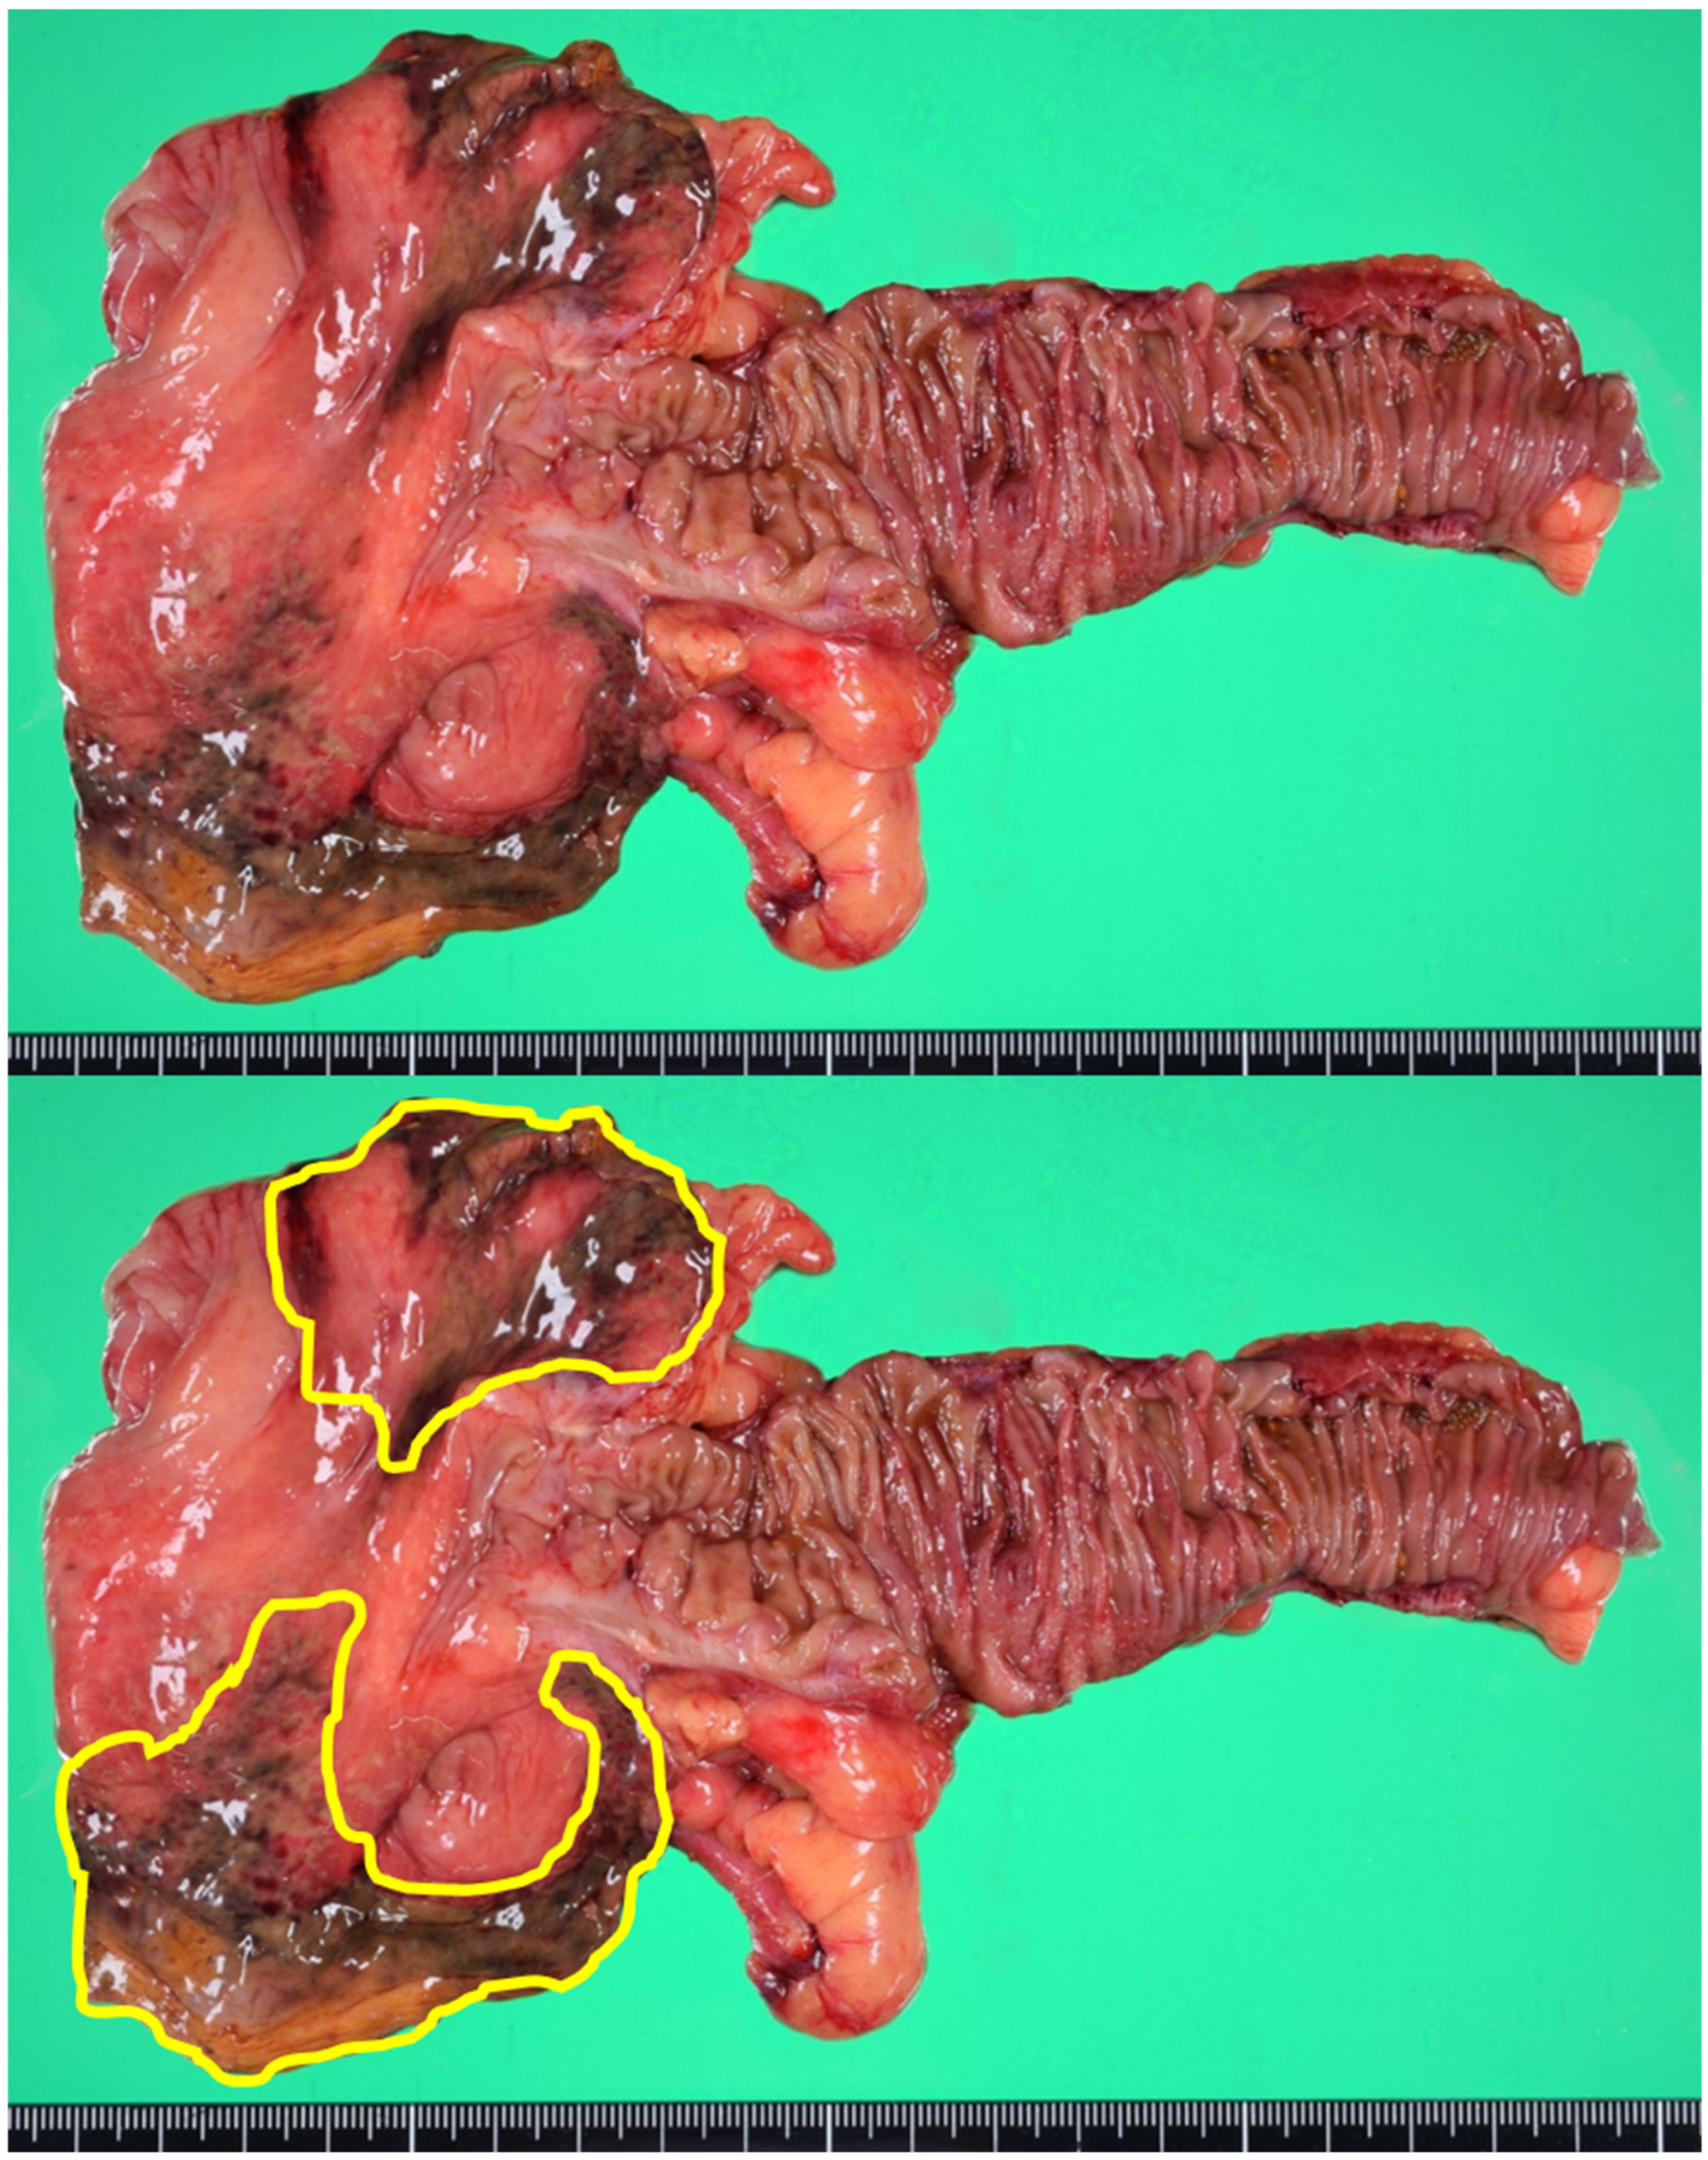

About 10 h after symptoms onset, we performed a laparoscopic-assisted ileocecal resection. After the resection of the damaged intestine, extracorporeal end to end anastomosis was performed. The specimen revealed localized ischemic change on the anti-mesenteric side of the cecum (Figure 3). Microscopically, the transluminal ischemic change was confirmed.

Figure 3.

The specimen showed localized ischemic change on the anti-mesenteric side of the cecum. The enclosed area in the lower picture showing the damaged wall.